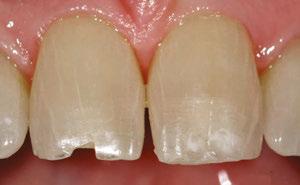

Case 2

A 3-year-old female presented with pulpal necrosis and abscess on #E and pulpal necrosis on #F. Extraction therapy or pulpectomy was offered. The family was highly motivated to retain #E and #F. The pulpectomy was performed with 0.02 K-Flex hand files, 3% NaOCl with a lateral vented needle, obturated with Vitapex (Neo Dental International Inc., Federal Way, Washington), a premixed paste of calcium hydroxide and iodoform. The access was filled with a HVGIC sealing the pulp therapy and increasing the clinical success by minimizing the potential for bacterial contamination. NuSmile ZR anterior crowns were selected as offering a full-coverage, esthetic, cemented restoration with no polymerization shrinkage when compared to a composite restoration. Crowns were cemented with NuSmile® BioCem (NuSmile, Houston, Texas). This is clinically beneficial as the provider would want to cement a restoration that provides limited microleakage minimizing the potential for bacterial contamination.15-17 At 6-month follow up, lesion healing had occurred with healthy gingival margins and no plaque accumulations (Figure 3).

A 4-year-old female presented with existing Silver Modified Atraumatic Restorative Technique (SMART) style restorations on #D, #E, #F, #G, and caries on other teeth. These anterior lesions

had been previously treated using SDF and covered with a HVGIC in a strip crown form. Though her lesions were stable from the clinical success of the SDF and HVGIC, these restorations were starting to fracture and demonstrate loss of material. The family wanted a more esthetic treatment option that would have a longer survivability. Additionally due to her high caries risk nature, a full coverage restoration with NuSmile® ZR anterior crowns were a more ideal solution in stabilizing her extensive decay pattern and covering staining from SDF therapy (Figure 4).

Figure 3: NuSmile® ZR Crowns were selected as a cementable full coverage restoration. At 6-month recall, apical tissues were healed with excellent gingival health Figure 4: SMART style restorations that were definitively restored with NuSmile® ZR Crowns as an esthetic option to cover SDF staining